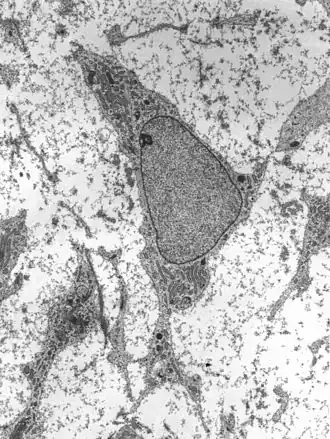

Human mesenchymal stem cells

Mesenchymal stem cells (MSC) or mesenchymal stromal cells, also known as medicinal signaling cells are known to be multipotent, which can be found in adult tissues, for example, in the muscle, liver, bone marrow and adipose tissue. Mesenchymal stem cells usually function as structural support in various organs as mentioned above, and control the movement of substances. MSC can differentiate into numerous cell categories as an illustration of adipocytes, osteocytes, and chondrocytes, derived by the mesodermal layer.[34] Where the mesoderm layer provides an increase to the body's skeletal elements, such as relating to the cartilage or bone. The term "meso" means middle, infusion originated from the Greek, signifying that mesenchymal cells are able to range and travel in early embryonic growth among the ectodermal and endodermal layers. This mechanism helps with space-filling thus, key for repairing wounds in adult organisms that have to do with mesenchymal cells in the dermis (skin), bone, or muscle.[35]